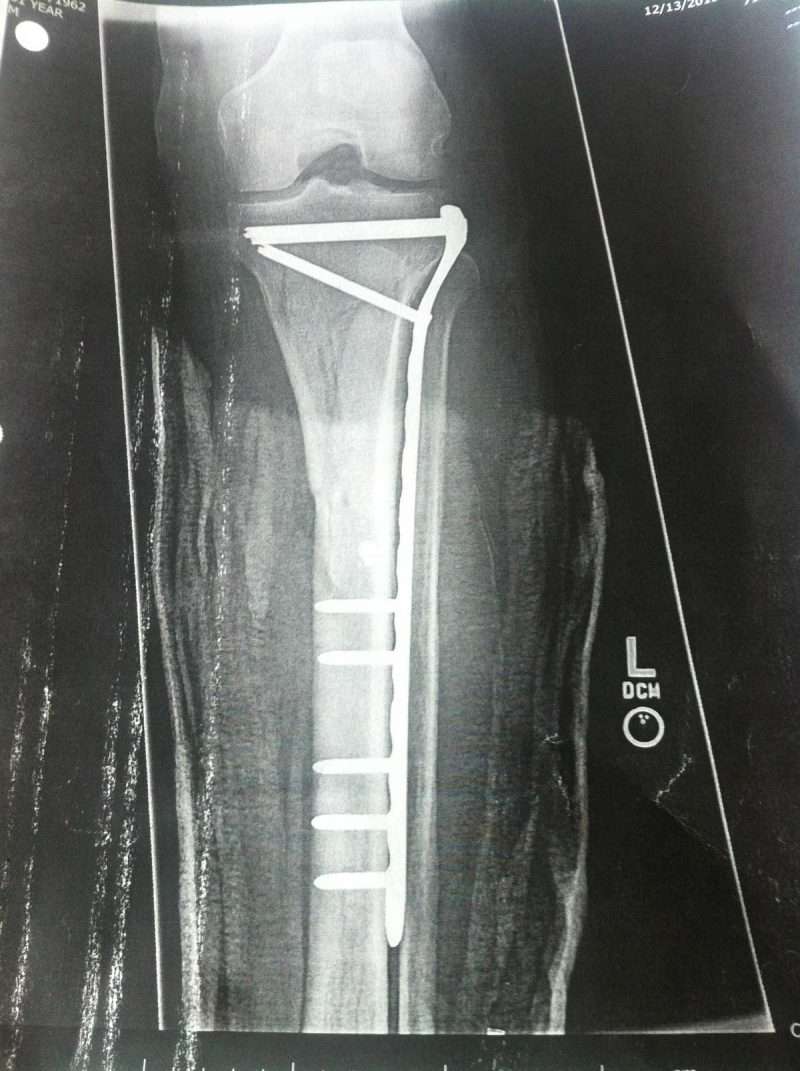

x ray of leg

I was halfway down a ladder that was perched against a frozen gutter.  The ladder slipped and I fell, snapping my leg upon touchdown.  But this isn’t a simple broken bone story.

The procedure went as planned.  I gained some new stainless accessories.  No drama.  However, things became complicated in the recovery room.  As the anesthesia wore off I was in terrible pain.  Much worse than before surgery.  Much worse than any other surgical trauma.  It was well beyond normal.